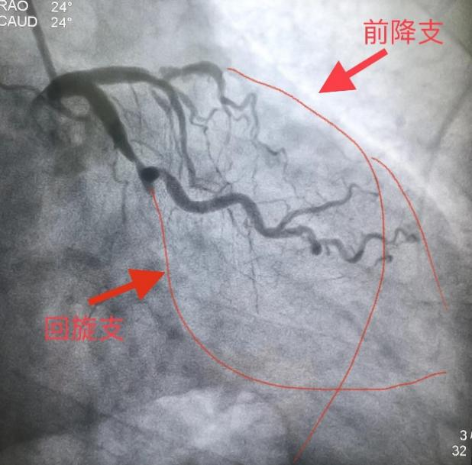

入院后立即完善术前检查和评估,第三天雷新军教授即带领景林德博士和李瑞峰住院医生为患者实施了手术,术中CAG显示:前降支7段和回旋支13段为CTO,因多次手术失败的原因,前降支7段存在明显的夹层和血肿病变,极大地增加了手术难度(图5)。经过缜密分析,雷新军教授决定首先尝试正向开通前降支CTO,若手术顺利再正向开通回旋支CTO,择期干预右冠脉。在不同体位造影指导下,雷新军教授仔细操控多种CTO导丝,历经约2小时终于成功开通了前降支和回旋支CTO,休息数天后又成功干预了右冠脉,手术效果良好(图6)。

图6 青海省人民医院PCI术后资料